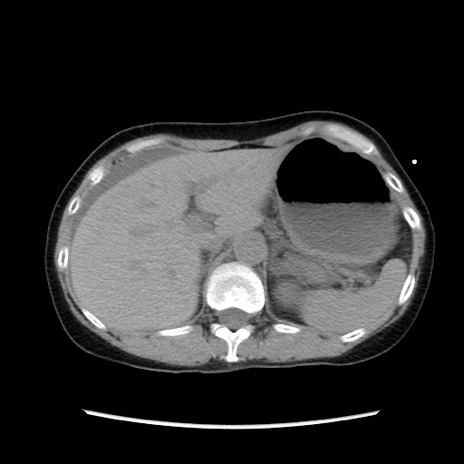

冠状断像

【症例】40歳代 女性

【主訴】上腹部痛、嘔気・嘔吐

【現病歴】約9時間前頃から急に上腹部痛、嘔気、嘔吐が出現。改善しないため救急要請。

【既往歴】子宮頚癌(広汎子宮全摘術、放射線療法)、腸閉塞

【身体所見】腹部:平坦、軟、腸雑音亢進、上腹部を中心に腹部全体に圧痛あり。

【データ】WBC 8400、CRP 0.03